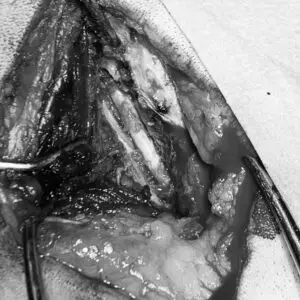

Experienced neurosurgery and neuro-diagnosis is supported by advanced imaging and experienced surgeons. From routine spinal surgery such as ventral slot, or hemilaminectomy to management of significant abnormality requiring pedicle screw repairs or fractures the neurology team are available for urgent and routine referrals.